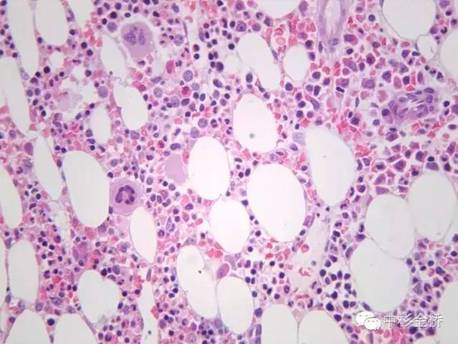

Rapidcal.Immuno脫鈣處理的骨髓標(biāo)本,易于2?m連續(xù)完整切片,鏡下結(jié)構(gòu)清晰,細(xì)胞核與漿顏色鮮艷;常規(guī)硝酸脫鈣的骨髓標(biāo)本,鏡下細(xì)胞核與漿顏色對比不明顯,染色質(zhì)不清晰。免疫組化實(shí)驗(yàn)中,Rapidcal.Immuno脫鈣處理的骨髓標(biāo)本,CD3、CD4、CD79a、CD20所標(biāo)記的T細(xì)胞和B細(xì)胞定位準(zhǔn)確,陽性表達(dá)強(qiáng),背景清晰。常規(guī)硝酸脫鈣的骨髓標(biāo)本,抗原部分丟失,標(biāo)記物陽性結(jié)果表達(dá)較弱,背景有部分非特異性著色。

免疫組化CD79a差

免疫組化CD79a好